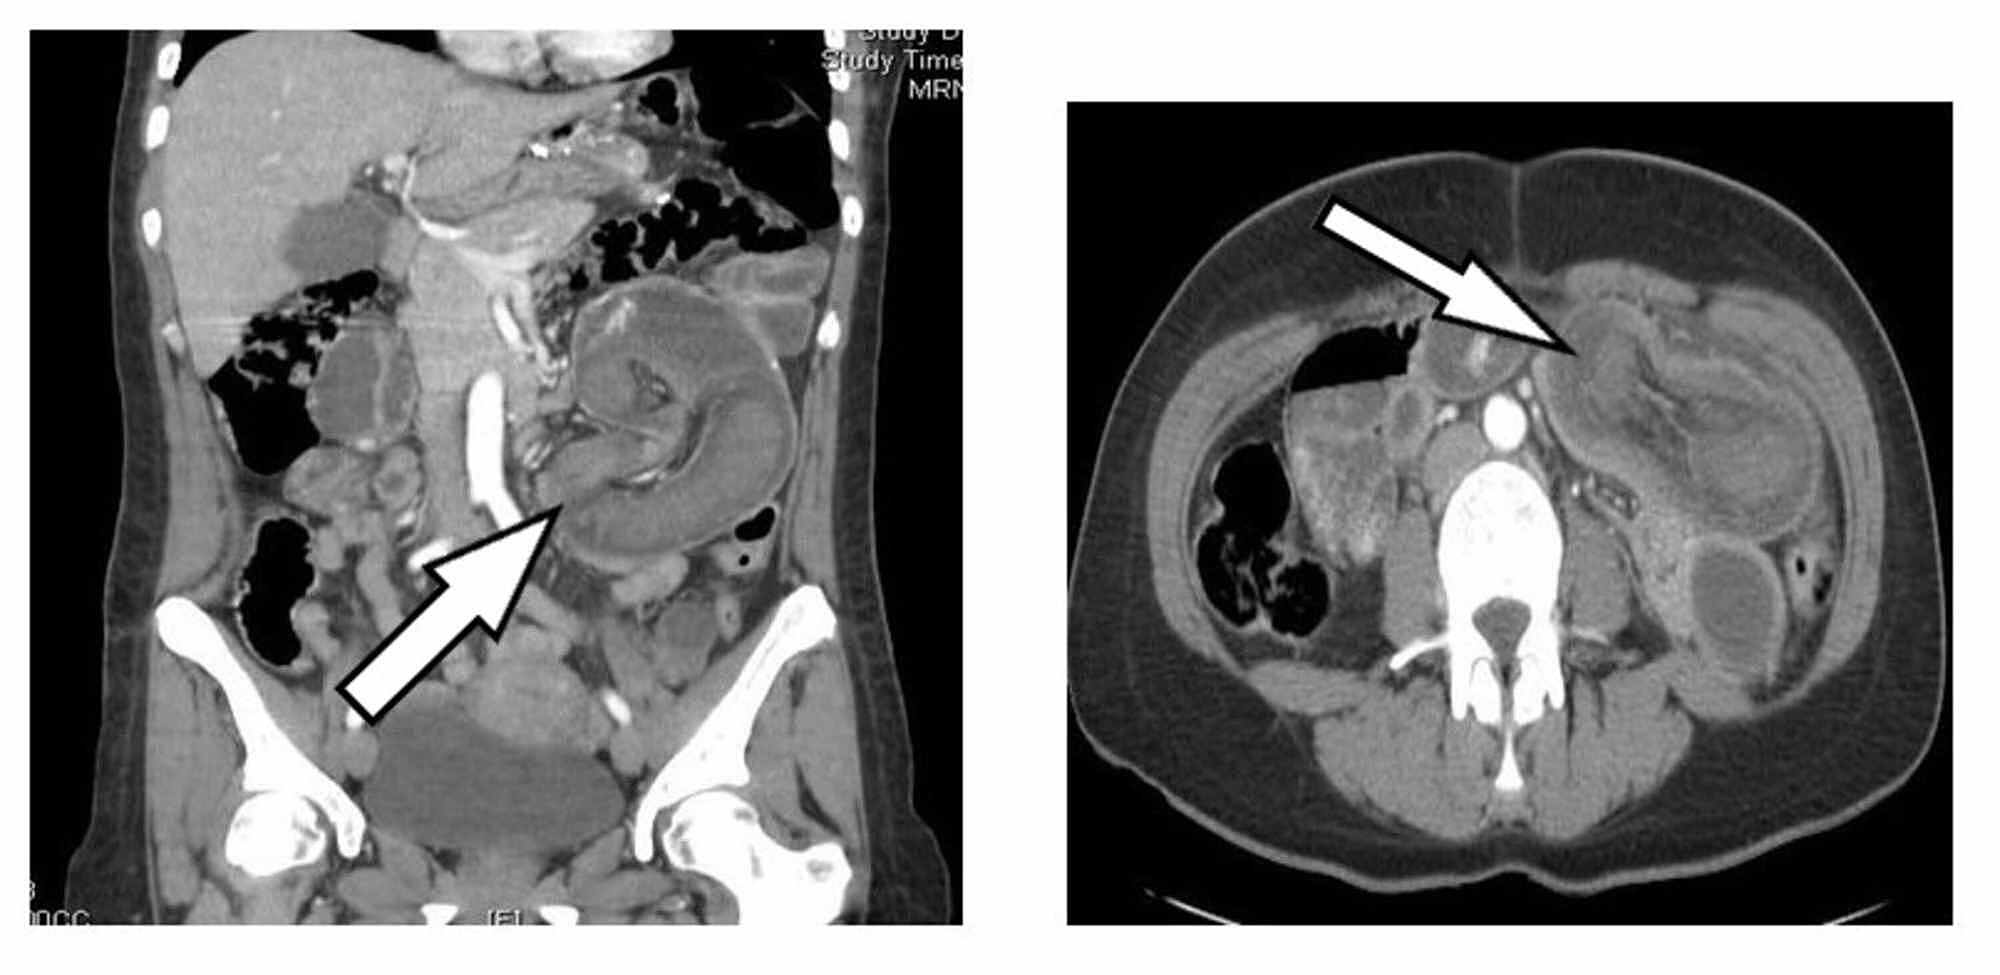

Abdominal/pelvic CT showing a large retrograde jejunogastric Gastric Bypass Intussusception Radiology It could cause abdominal pain and. Intussusception occurs when one segment of the bowel is pulled into itself or a neighboring loop of the bowel by peristalsis. Prompt diagnosis is critical as. It is an important cause of an acute abdomen in. With unclear risk factors and a variable presentation,. Gastric Bypass Intussusception Radiology.